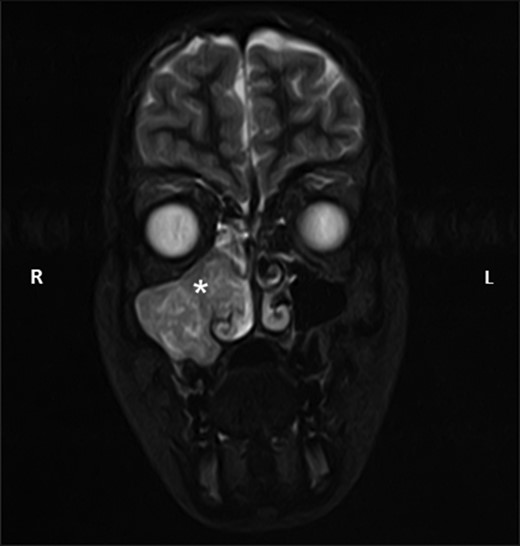

Coronal STIR sequence magnetic resonance image taken as part of the diagnostic investigations, showing the same antrochoanal mass (white asterisk) showing extension into the nasal cavity. L, left; R, right.